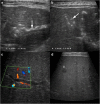

Methods: Indubitably, imaging is the mainstay for detection of tubercular hepatic lesions which display a broad spectrum of imaging manifestations on different modalities. While sonography and computed tomography (CT) findings have been described in some detail, there is a paucity of literature on magnetic resonance imaging (MRI) features. Due to a significant overlap with other commoner and similar appearing hepatic lesions, hepatic tuberculosis is often either misdiagnosed or labelled as indeterminate lesions. This article is a compendium of cases highlighting the spectrum of imaging patterns that can be encountered in patients with isolated primary hepatic tuberculosis as well as disseminated (secondary) disease. Rare patterns of primary disease such as tubercular cholangitis, hypervascular liver masses, and those with vascular complications are also illustrated and discussed.

Conclusions: Imaging plays a valuable role in the detection of tubercular hepatic lesions. Also, imaging can be helpful in their characterisation and for assessing associated complications.

Teaching points: • Hepatic TB has myriad imaging manifestations and is often confounded with neoplastic lesions. • Imaging patterns include miliary TB, macronodular TB, serohepatic TB and tubercular cholangitis. • Concurrent splenic, nodal or pulmonary involvements are helpful pointers towards the diagnosis. • Miliary calcifications along the bile ducts are characteristic of tubercular cholangitis. • Histological/microbiological confirmation is often necessary to confirm the diagnosis.